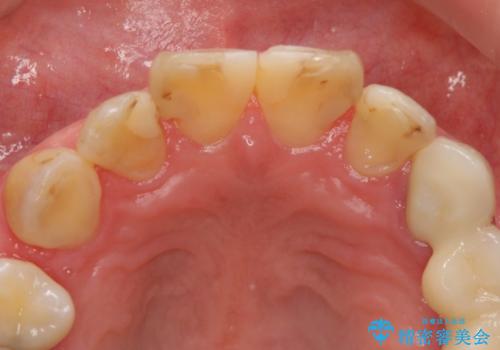

その後3年間来院がなく、その間に前歯の虫歯の進行があり、治療を行いました。

やはり、樹脂で虫食い状になってしまうと虫歯が進行しやすくなっているためクラウンがおすすめです。

下の前歯との距離(クリアランス)が大きくは取れなかったため、ジルコニアクラウンではなくe-maxクラウンにしました。